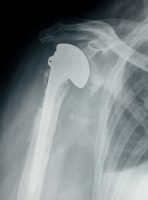

Abbildung 2: Hemiprothese, Totalprothese

Mineralstoffwechsel

Prothese

Röntgenbild

Schultergelenk